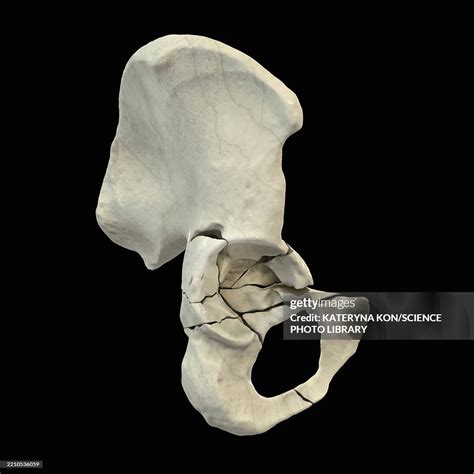

The acetabulum is a cup-shaped socket in the pelvis that articulates with the femoral head to form the hip joint. It is composed of the ilium, ischium, and pubis bones, which fuse together during development. The acetabulum provides a stable and secure environment for the femoral head, allowing for a wide range of motion while maintaining joint integrity.

Classification of Fractures of the Acetabulum

Fractures of the acetabulum are classified based on the pattern and location of the fracture. The most commonly used classification system is the Letournel and Judet classification, which categorizes acetabular fractures into ten distinct types:

Both Columns Fracture involving both the anterior and posterior columns